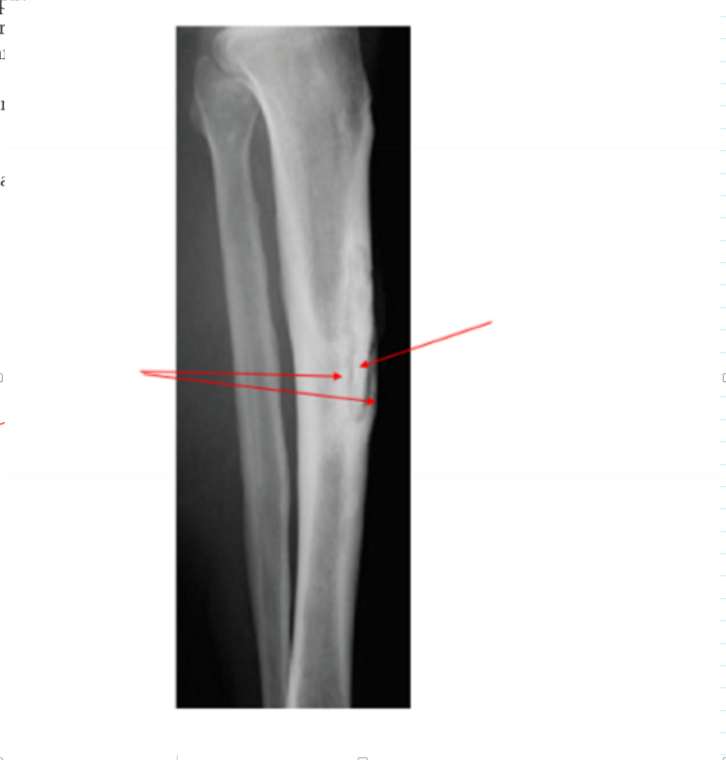

Identify